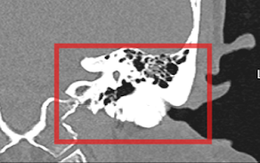

Giảm thính lực do lồi xương ống tai ngoài hiếm gặp

Một người phụ nữ bị giảm thính lực do lồi xương ống tai ngoài hiếm gặp. Các bác sĩ Bệnh viện TP Thủ Đức đã phẫu thuật và lấy lại thính lực thành công cho người bệnh này.